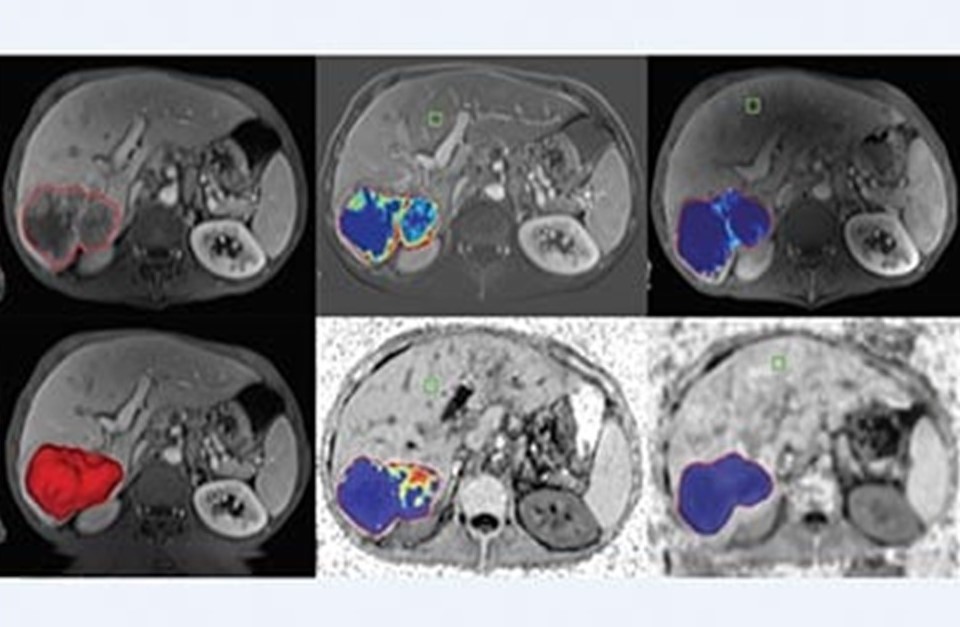

Philips IntelliSpace IX/LX Workstation for CT Oncology

PHILIPS